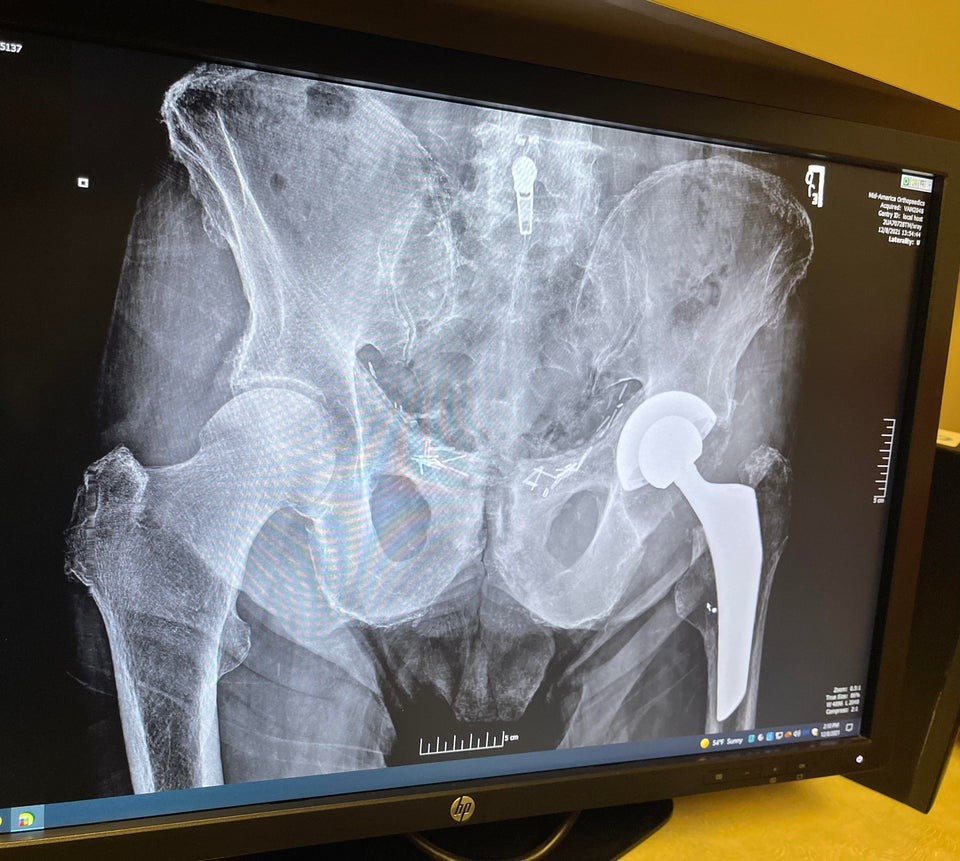

Слева - новое бедро

Таз после операции

ЗЫЫ. Бедро слева. Медики автоматом это видят, у меня даже иногда сложности с групповыми фото, типа "ХХХ второй слева"... а вот обычным юзерам сложнее, им бедро справа...